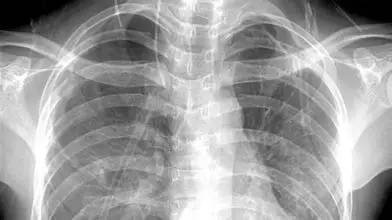

3、胸部——粗看X光片,细看CT

X光胸片可粗略检查心脏、主动脉、肺、胸膜、肋骨等,可以检查有无肺纹理增多、肺部钙化点、主动脉结钙化等。

胸部CT检查显示出的结构更清晰,对胸部病变检出敏感性和显示病变的准确性均优于常规X光胸片,特别是对于早期肺癌确诊有决定性意义。但是,CT检查的辐射剂量高于X光。核磁对于肺部疾病的诊断,应用非常有限。